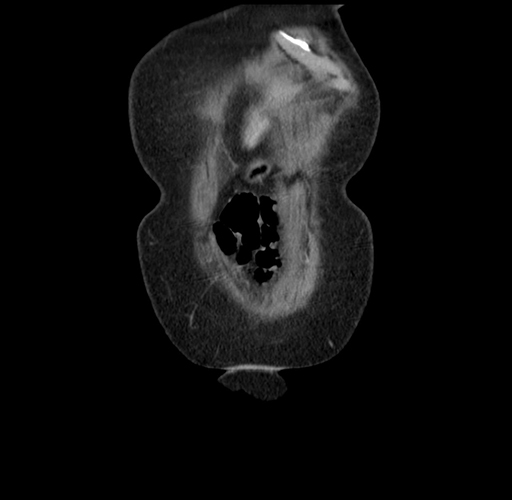

Pre-Chemo: Axial Venous